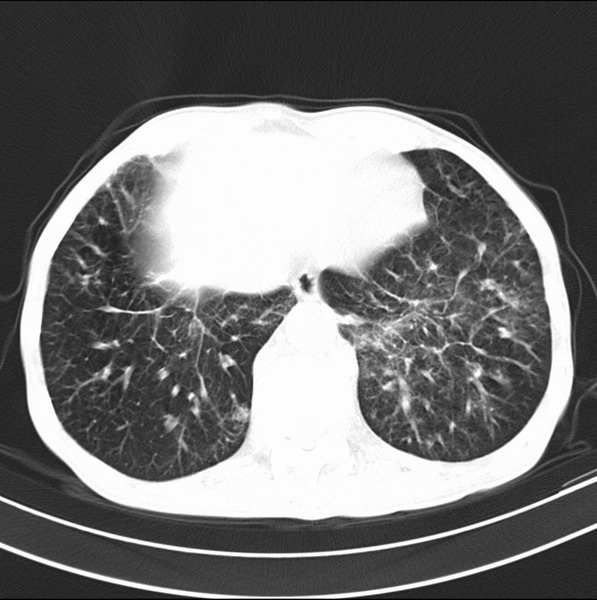

标题: CT19600:能否诊断为转移?

女、55

3年前盲肠癌、一年半前诊断膀胱癌,现在呼吸困难,临床考虑为肺转移

请问胸部ct如何诊断?能否排除淋巴管炎,纵隔窗没有问题。

炎性并间质纤维化,请询问病史,如用过平阳霉素或其他化疗药.可能为药物引起的间质纤维化.